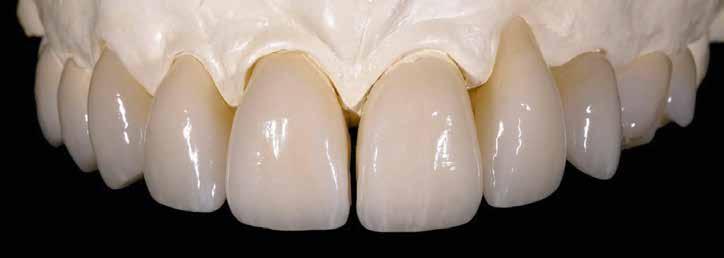

A koronákat IPS e.max ZirCAD Prime (Ivoclar Vivadent) anyagból martuk ki. E cirkónium-dioxid korongok előállítása Gradient Technology (GT) segítségével történik, az alap-

anyag egyidejűleg nagy szilárdságú és transzlucens is. Ez több szempontból előnyös: először is adott a jó stabilitás – a biaxális hajlítószilárdság 1200 Mpa, a törési szilárdság nagyobb 5 Mpa m1/2-nál. Ezzel hosszú élettartamú koronák és nagy fesztávolságú hidak készítésére is alkalmas. Ugyanakkor a kerámia teljesen fokozatmentes színátmenettel és nagyfokú transzlucenciával is rendelkezik, így bevethető a magas esztétikájú frontpótlások területén is. A megoldandó esettől függően teljes, részben vagy egészen leplezett formában is alkalmazható, akár egy pótláson belül kombinálva. Ezáltal az IPS e.max ZirCAD Prime valóban „One-Disc-Solution” (egy korong mindenre megoldás – a ford.), amelynek előnyeit maximálisan kihasználhatjuk minden páciens számára. Ebben az esetben enyhén redukált koronavázakat alakítottunk ki, amelyet az IPS e.max ZirCAD Colouring Liquids, az IPS e.max Ceram leplezőrendszere, valamint festék- és glazúrkészlete segítségével egészítettünk ki (3–7. képek).

3. kép: Enyhén redukált anatómiájú koronák IPS e.max ZirCAD Prime anyagból – infiltrációs folyadékkal enyhén színezve a nyaki területen

7. kép: A befejezett IPS e.max ZirCAD Prime koronák a mintán.

4. kép: A szinterezett koronák a mintán.